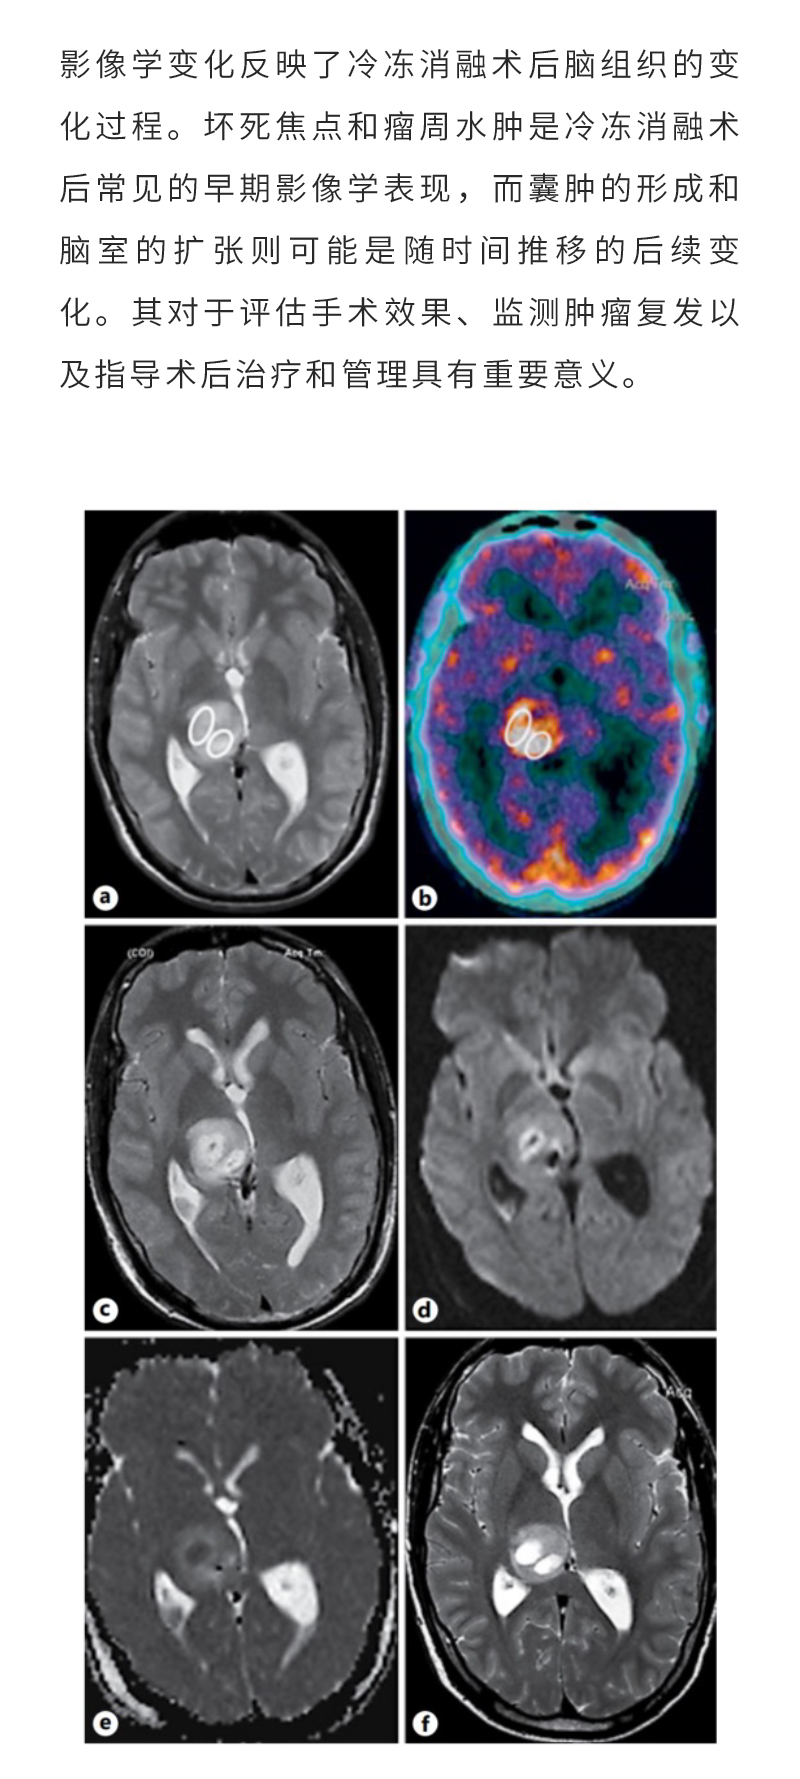

日本特黄特色a大片免费高清观看视频_亚洲午夜综合_一女被两男3p做爰视频_丰满少妇久久_欧美激情在线第一页_久久五月激情_亚洲成人激情在线_滚床单又黄又肉细节描写_日韩av综合在线观看_人妖一级片